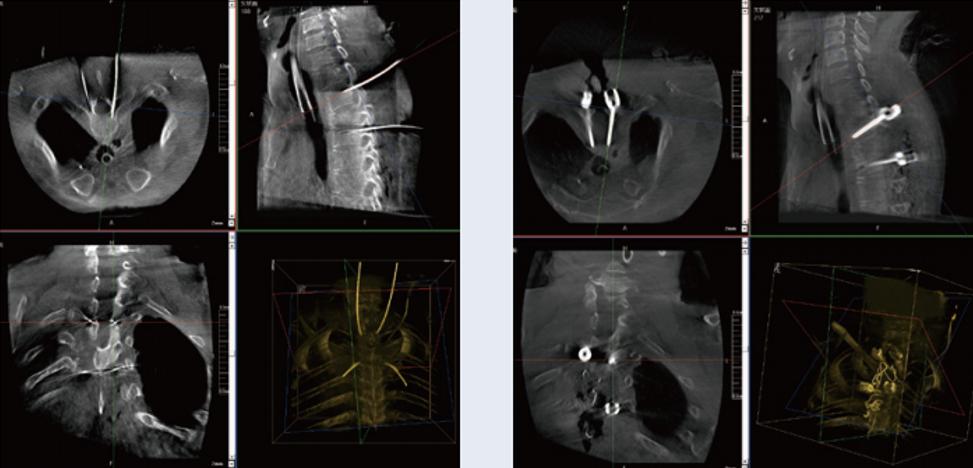

螺釘規(guī)劃后的圖像

植入螺釘后的圖像

術(shù)中三維C臂與骨科導(dǎo)航機器人配合應(yīng)用,實現(xiàn)準確定位,確保了手術(shù)安全、高效完成。術(shù)后二維、三維影像顯示手術(shù)效果良好,達到預(yù)期目的。